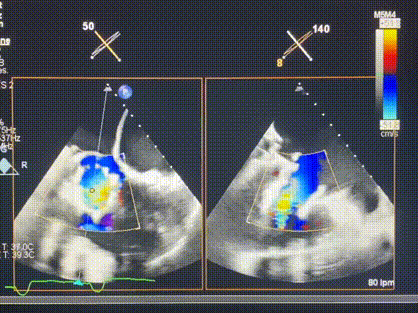

術(shù)后超聲顯示僅殘余微量瓣周漏

LuX-Valve Plus經(jīng)血管三尖瓣置換系統(tǒng)此次“出海”圓滿完成,術(shù)后Rodrigo Estévez-Loureiro教授對LuX-Valve Plus經(jīng)血管三尖瓣置換系統(tǒng)的器械性能和治療效果大為稱贊,認為LuX-Valve Plus的手術(shù)體驗非常好。術(shù)后即刻超聲顯示三尖瓣反流幾乎完全消失,血流動力學改善顯著,患者恢復快。在面對復雜解剖結(jié)構(gòu)、超聲影像質(zhì)量不佳、有起搏導線干擾時,Lux-Valve Plus也體現(xiàn)了極強的適應(yīng)性。Thomas Modine教授和Anson Cheung教授也肯定了LuX-Valve Plus術(shù)中操作的便捷性,認為LuX-Valve Plus容錯率高,對術(shù)中影像的依賴較小,后期希望可以更多的應(yīng)用LuX-Valve Plus三尖瓣置換系統(tǒng)于臨床實踐,讓更多的三尖瓣重度反流患者盡早獲益,改善預后。